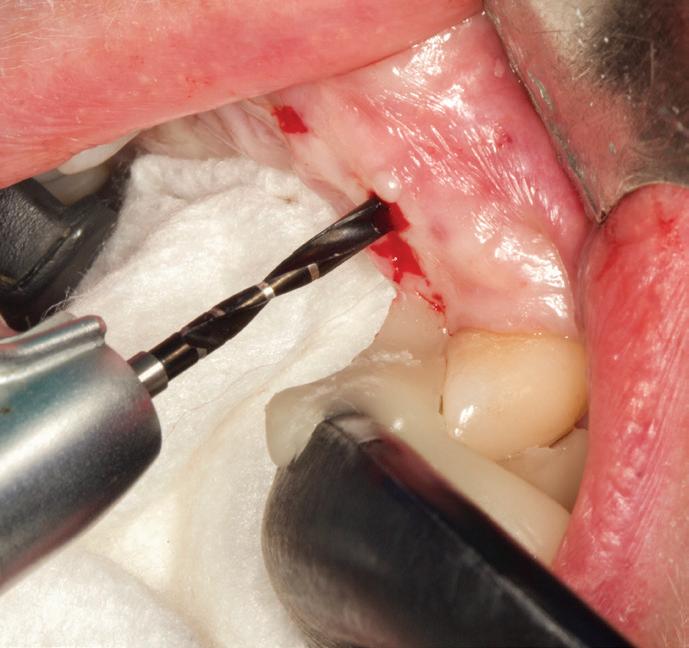

Această tehnică este o opțiune atunci când nu există suficient țesut gingival keratinizat și este preferată atunci când caninul impactat este situat mezial față de incisivul lateral. Lamboul trebuie fixat și adaptat la dinte. Dezavantajele includ riscul de recesie și marginea gingivală neregulată, alături de necesitatea unei intervenții chirurgicale osoase extinse. Se efectuează incizii verticale, iar lamboul este deplasat într-o direcție laterală sau apicală. Se recomandă un design al lamboului în care baza și zona coronară sunt fie la aceeași lățime, fie mai înguste la bază, cu o grosime de 4-5 mm, astfel încât lamboul să fie suficient de lat meziodistal, extinzându-se cu 1,5 mm dincolo de unghiul dintelui (fig. 6, 7).

Osul acoperitor trebuie îndepărtat cu chiuretă sau freză diamantată pentru a expune porțiunea liberă a coroanei. Lamboul se poziționează apoi la CEJ și se fixează cu suturi periostale pentru o stabilitate mai mare. În funcție de gradul de impactare a caninului, se poate plasa un pansament parodontal, astfel încât țesutul să nu se închidă. Bracketul este plasat fie în momentul procedurii, fie la 10 zile postoperator. Dacă respectivul canin este situat prea apical, se preferă tehnica închi-

să. În general, deplasarea ortodontică începe la 4-6 săptămâni după expunerea chirurgicală. Când foliculul ce înconjoară caninul este larg, incizia lamboului trebuie făcută peste limitele acestuia, pentru a permite adaptarea optimă a lamboului la coroană și os. Pentru a determina buna adaptare a lamboului, atunci când buza se mobilizează, acesta ar trebui să rămână staționar.